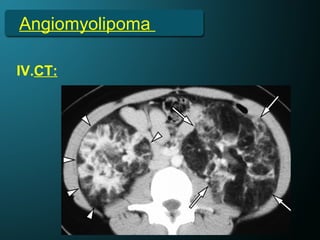

Angiomyolipoma

IV.CT: